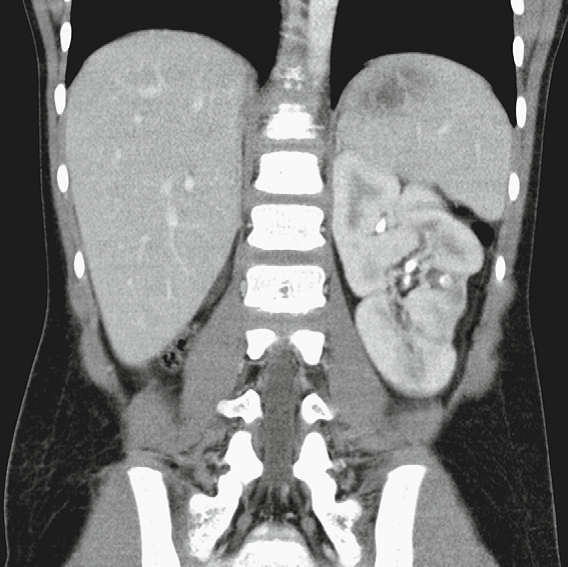

The left and right kidneys

should normally be within 1 cm of each other.

If there is a discrepancy of more than 1 cm, an

underlying abnormality should be suspected.

The left and right kidneys should normally be within 1 cm of each other. If there is a discrepancy of more than 1 cm, an underlying abnormality should be suspected.

Vesicoureteral Reflux Grading

Most low-grade VUR resolves sponta- neously by the age of 5 to 6 years unless there is an underlying anatomic abnormality.

Figure example:

Right side - Grade 2

Left side - Grade 5